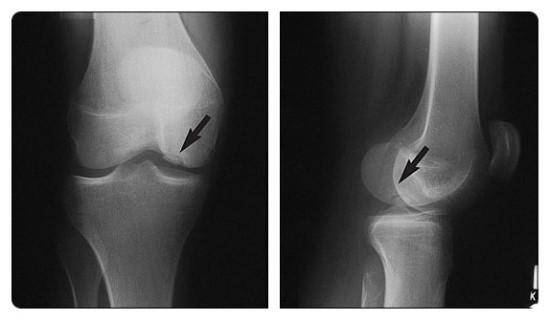

22. 외측 슬개골 탈구의 징후에 대해 열거하라.

• 외측 대퇴과의 후외측 방면과 내측 슬개골 후관절의 내측 방면에서의 상호간 골 타박상

• 슬개대퇴 연골 손상

• 내측 슬개지대 또는 내측 슬개대퇴인대 또는 양쪽 모두의 손상

• 관절 삼출액

얕은 슬개골 절흔의 존재는 이러한 손상이 초래되는 경향이 있을 수 있다. (그림 46-10)

△ 그림 46-10. 일과성 외측 슬개골 탈구 (Transient lateral patellar dislocation)

슬개골을 지나는 축면 지방 포화 T2 강조영상은 외측 대퇴과의 후외측 방면(굵은 화살표)과 내측 슬개골 후관절(점선 화살표)에서의 상호 골타박상(높은 신호)을 보여준다. 내측 지대(빈 화살표)는 주위 부종으로 두꺼워져 있고, 부분 파열을 나타낸다. M = 내측, L = 외측